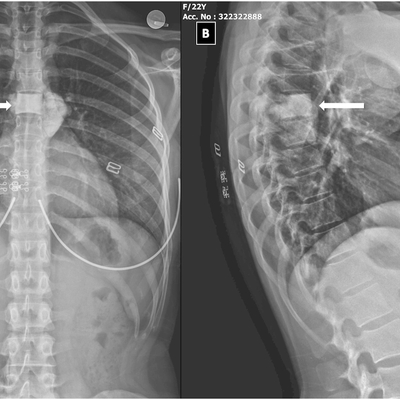

Click on an image below to view more info.